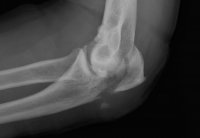

Pretty f'n benign. Riding along a ridge with a kinda a wash between the one I was on and another one. Both prolly 8' high with about 3' of a wash between them. So I go down the one and start to go up the other side. The one I go down is kinda hard packed but the one I start going up is kinda soft so the bike starts to sink in. I figured I wasn't gonna make it so I turn to the left, which is the downhill slope of the whole area but the bike kinda sinks in some more and I figured the bike was gonna stall so I swing my right foot over the back of the bike to get off the bike but now I am facing uphill so I start falling backwards. I was prolly only 4' up the hill but gravity takes over and my lack of grace and my, uh, er, girth cause me to kinda just stumble backwards down the hill to the bottom. When I get to the bottom I fall on my ass and my...…..elbows. And wouldn't you know it, my left elbow found 1 of the 3 boulders in the whole area.....SMACK! With all my weight it drives my Humerus bone (really not funny) right through my Ulna bone (elbow) shattering it....Oh damn! More racing titanium. Let’s hear the story.

When they finally unwrapped all the bandages my buddies had put on they got to the last one. My wife went, "ooohhh", and left the room. The Dr handed me a gauge pad and said "hold it here with some pressure, I'll be right back"